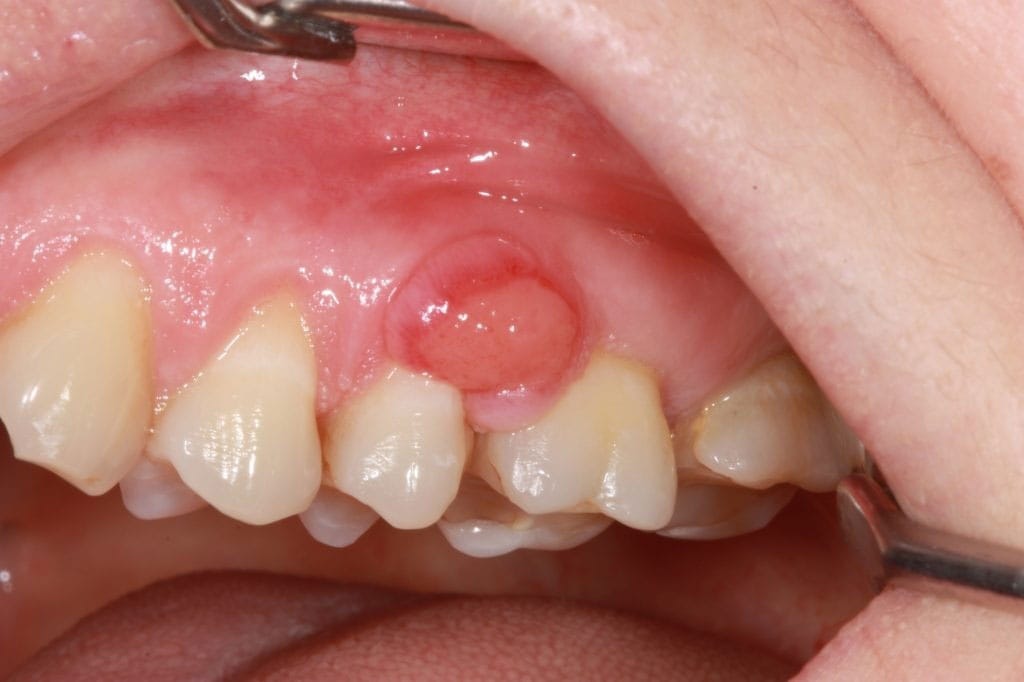

Pemfigoid är en heterogen grupp av kroniska, autoimmuna sjukdomar som ger symtom i form av blåsor/ulcerationer på hud och slemhinnor. Pemfigoid medför risk för stort lidande och ofta en lång behandling med flera biverkningar. Det är framförallt äldre personer som drabbas och incidensen har ökat de senaste åren.

- Slemhinnepemfigoid (eng. Mucous membrane pemphigoid – MMP). Munslemhinnan är den vanligaste lokalisationen (ca 85% av patienterna) och näst därefter drabbas ögonslemhinnan-konjunktivan (ca 65%). Även andra slemhinnor i nasopharynx, esophagus, larynx och på genitalia kan vara involverade, liksom huden.